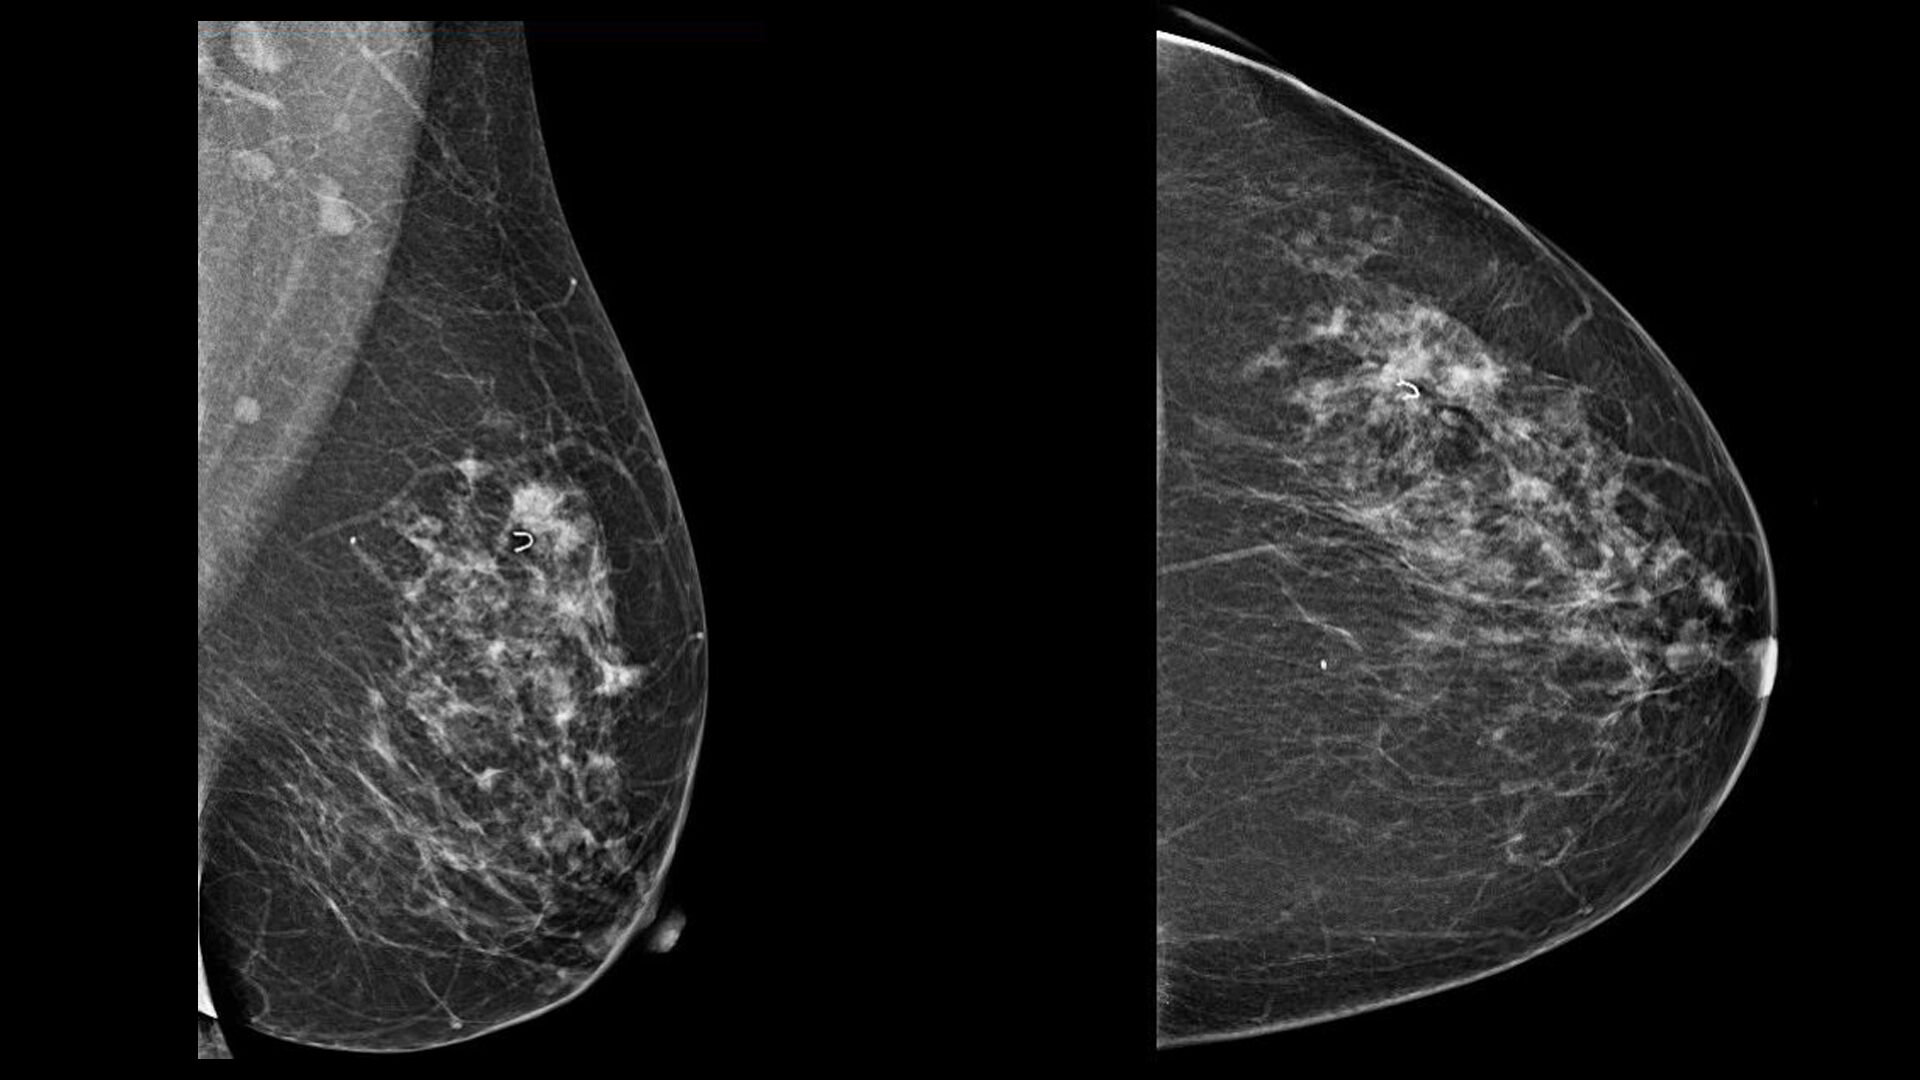

Новообразование в головном мозге. Презентация опухоль мозга. Опухоли головного мозга презентация. Злокачественная фиброаденома молочной железы. Фиброаденома молочной железы Размеры для операции. Фиброаденома молочной железы маммография. Листовидная опухоль гистология.

Злокачественная фиброаденома молочной железы. Фиброаденома молочной железы Размеры для операции. Фиброаденома молочной железы маммография. Листовидная опухоль гистология. Доброкачественная опухоль. Доброкачественныеопкхоли. Клетки, образующие доброкачественную опухоль:. Строение доброкачественной опухоли.

Гепатомегалия. Симптомы гепатомегалии. Умеренное увеличение печени. Умеренная гепатомегалия. Маммография косая проекция укладка. Маммография молочных желез. Маммография это исследование. Рентгеновская маммография.

Маммография косая проекция укладка. Маммография молочных желез. Маммография это исследование. Рентгеновская маммография. Подчелюстная слюнная железа на рентгене. Сиалография слюнных желез. Рентгенография слюнных желез. Контрастная сиалография слюнных желез.

Подчелюстная слюнная железа на рентгене. Сиалография слюнных желез. Рентгенография слюнных желез. Контрастная сиалография слюнных желез. Фиброаденома молочной железы дифференциальный диагноз. Новообразование молочной железы фиброаденома. Диф диагноз фиброаденомы молочной железы. Фиброаденома молочной железы 30мм-37мм.

Фиброаденома молочной железы дифференциальный диагноз. Новообразование молочной железы фиброаденома. Диф диагноз фиброаденомы молочной железы. Фиброаденома молочной железы 30мм-37мм. Диагностические критерии глиомы головного мозга. Особенности опухолей лобной доли. Клиника опухоли затылочной доли головного мозга. Симптомы, характерные для опухолей лобной доли.

Глиобластома мультиформная степень 4. Неоперабельная глиобластома головного мозга.. Глиобластома лобной доли мрт. Глиобластома злокачественная опухоль агрессивная. Филлоидная фиброаденома молочной железы УЗИ. УЗИ признаки доброкачественных опухолей молочных желез. Доброкачественная опухоль молочной железы на УЗИ. Опухоль молочной железы на УЗИ.

Магнитно-резонансная томография легких. Магниторезонансная томография легких. Магнитно ядерная томография. Ядерно-магнитно-резонансная томография. Саркома молочной железы на маммографии. Фибросаркома маммография. Саркома молочной железы рентген. Болезнь Педжета молочной железы маммография.

Саркома молочной железы на маммографии. Фибросаркома маммография. Саркома молочной железы рентген. Болезнь Педжета молочной железы маммография. Типы роста опухолей. Инфильтративный Тип роста. Инфильтрирующий рост опухоли.

Опухоли задней черепной ямки. Объемное образование задней черепной ямки. Опухоли задней черепной ямки клиника. Канцер молочной железы. Онкология грудной железы. Онкологические заболевания груди. Опухоль молочной железы.

Канцер молочной железы. Онкология грудной железы. Онкологические заболевания груди. Опухоль молочной железы. Рентгеновские методы обследования. Рентгенологические методы исследования. Методики рентгенологического исследования. Методика рентген исследования.

Рентгеновские методы обследования. Рентгенологические методы исследования. Методики рентгенологического исследования. Методика рентген исследования. Очаговое образование молочной железы фиброаденома. Фиброзно-жировая инволюция молочных желез что это такое. Объемное образование в молочной железе. Злокачественные образования молочной железы.

Очаговое образование молочной железы фиброаденома. Фиброзно-жировая инволюция молочных желез что это такое. Объемное образование в молочной железе. Злокачественные образования молочной железы. Фиброламеллярная карцинома печени мрт. Фиброламеллярная карцинома печени кт. Доброкачественная опухоль печени мрт. Гепатоцеллюлярная карцинома мрт.

Опухоль печени доброкачественная кт. Первичные злокачественные опухоли печени. Злокачественные новообразования печени кт. Первичные и Метастатические опухоли печени. Маммография. Маммограмма молочных желез. Маммография после 40 лет проводится.

Маммография. Маммограмма молочных желез. Маммография после 40 лет проводится. Виды роста злокачественных опухолей. Рост злокачественных новообразований. Злокачественные опухоли характеризуются. Форма злокачественной опухоли.

Метастатическое поражение печени. Метастатические опухоли печени. Злокачественные образования печени. Молочная железа маммография. Мастопатия на маммографии. Опухоль молочной железы маммограмма. Рик молочной железы маммографич.

Молочная железа маммография. Мастопатия на маммографии. Опухоль молочной железы маммограмма. Рик молочной железы маммографич. Опухоль головного мозга симптомы. Новообразование в головном мозге. Раковые заболевания головного мозга. Объемное образование головного мозга.

Терминальная стадия онкологии. Опухоль грудной стенки кт. Опухоль в терминальной стадии. Маммография молочных желез объемное образование. Опухоль молочной железы. Онкология молочной железы. Опухольмолочныйжелезы.

Маммография молочных желез объемное образование. Опухоль молочной железы. Онкология молочной железы. Опухольмолочныйжелезы. Доброкачественная злокачественная опухоль головного мозга мрт. Глиома головного мозга мрт. Опухоль головного мозга на кт.